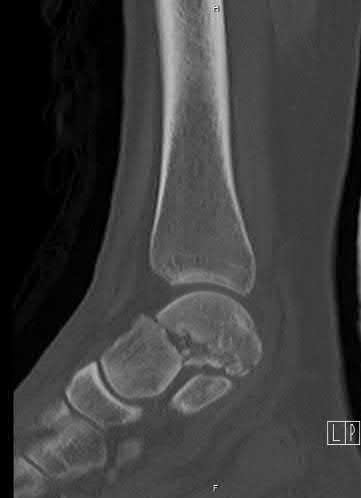

A 28-year-old male sustains a severe hyper-dorsiflexion injury to his ankle in a motor vehicle accident, resulting in a Hawkins Type III talar neck fracture. Which of the following arteries provides the predominant blood supply to the body of the talus, placing it at significant risk for avascular necrosis in this injury?

Explanation

The artery of the tarsal canal, which is a branch of the posterior tibial artery, provides the dominant blood supply to the talar body. In a Hawkins Type III fracture (talar neck fracture with subtalar and tibiotalar dislocation), the blood supply from the artery of the tarsal canal, the artery of the sinus tarsi, and capsular vessels are disrupted, leading to an avascular necrosis (AVN) rate approaching 100%.